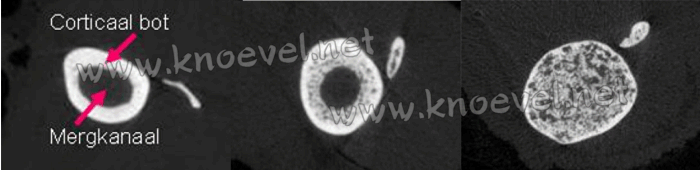

Niet satijn (ca. 6 jaar), satijn met beginnende OD (4 jaar), satijn met gevorderde OD (2 jaar)

Let op de verschillen. De tibia (scheenbeen) van een niet-satijn cavia heeft een normaal mergkanaal: de donkere ruimte in het midden van het bot, aangegeven door een pijl. Deze structuur verdwijnt naarmate de ziekte vordert. Bij ernstige satijnziekte wordt het bot homogeen opgevuld met weefsel, zodat het mergkanaal verdwijnt.

De veranderingen in de interne structuur van het bot zijn opmerkelijk. Hieronder ziet u een dwars doorsnede door het cavia onderbeen (midden in het scheenbeen). Het normale scheenbeen (in doorsnede) bestaat uit een vrij groot kalkarm (donker) mergkanaal, omringd door een vrij dun kalkrijk (wit) corticaal bot, zoals aangegeven door de pijlen. Corticaal bot wordt progressief vervangen door poreus bot (veel dikker dat de oorspronkelijke structuur); daarbij verdwijnt het mergkanaal. De botten worden dus "massief" (met ziekelijk weefsel), en ontdaan van merg. We kunnen ervan uit gaan dat bij ernstige OD de aanmaak van nieuwe bloedcellen ook ernstig zal afnemen.